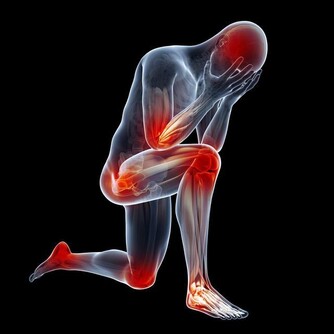

腦血栓,離我們遠嗎?

腦血栓不但影響患者身心健康嚴重的甚至導致癱瘓。

那麼,腦血栓的前兆都有哪些呢?

得了腦血栓又會有哪些癥狀呢?為家人,看一眼!腦血栓前兆